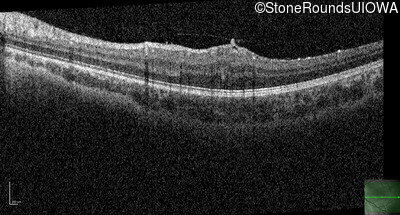

This 9 year old male was noted to have some crossing of his eyes at 2 months of age and the eye exam which followed identified a retinal lesion in the right eye. When he was six years old an epiretinal membrane was noted in his left eye. Two years later it was decided that it was a thin hamartoma in that eye as well. He underwent neuroimaging at age 7 which identified bilateral acoustic neuromas.